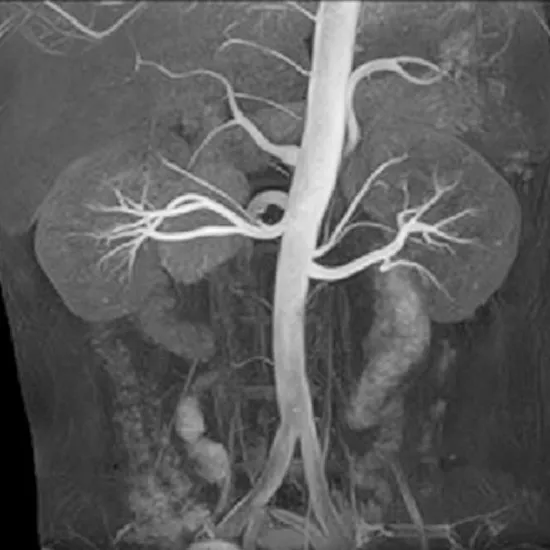

This test is conducted to see deep and superficial veins of the lower limb. This radiation-free examination uses a strong magnetic field and radio waves to create detailed pictures of abnormal areas.

The doctor prescribes this test to understand the current condition of veins including suspected inflammation, blockage and blood clots.

MR Venography of the Left Lower Limb With Contrast is a Magnetic Resonance Imaging non-invasive medical diagnostic tool using contrast for the detection of abnormalities related to the deep and superficial blood vessels of lower limbs.

MR Venography Left Lower Limb With Contrast shows deep blood vessel abnormalities in the lower limbs.